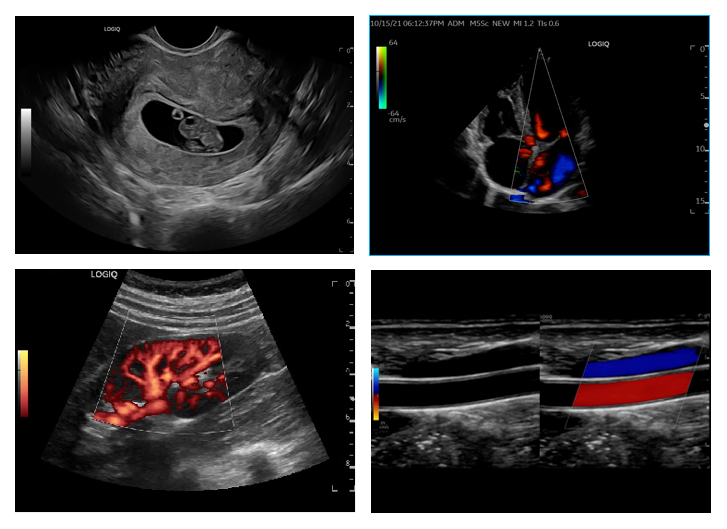

这款GE LOGIQ Fortis 第5代彩超设备在图像质量上实现了质的飞跃。其卓越的整场均匀性和空间分辨率,使得成像更加清晰、精确。此外,该设备还搭载了多项先进的血流成像技术,包括非多普勒原理的B-flow灰阶血流成像(类造影)、R-flow二维立体血流成像以及MVI超微细血流成像。

这些技术的运用,使得医生能够在二维图像上直观地观察到血流的动态情况,甚至能够精确显示出细小血管的结构,从而极大地提高了诊断的准确性和可靠性。